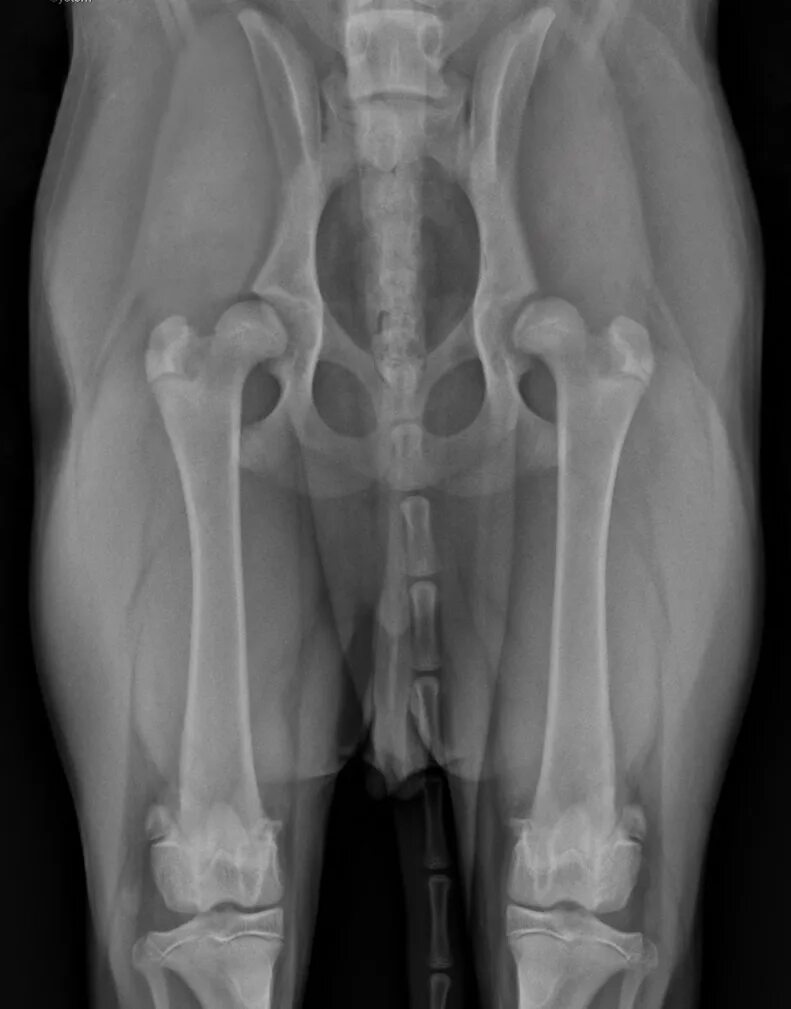

Дисплазия тазобедренного сустава мкб 10